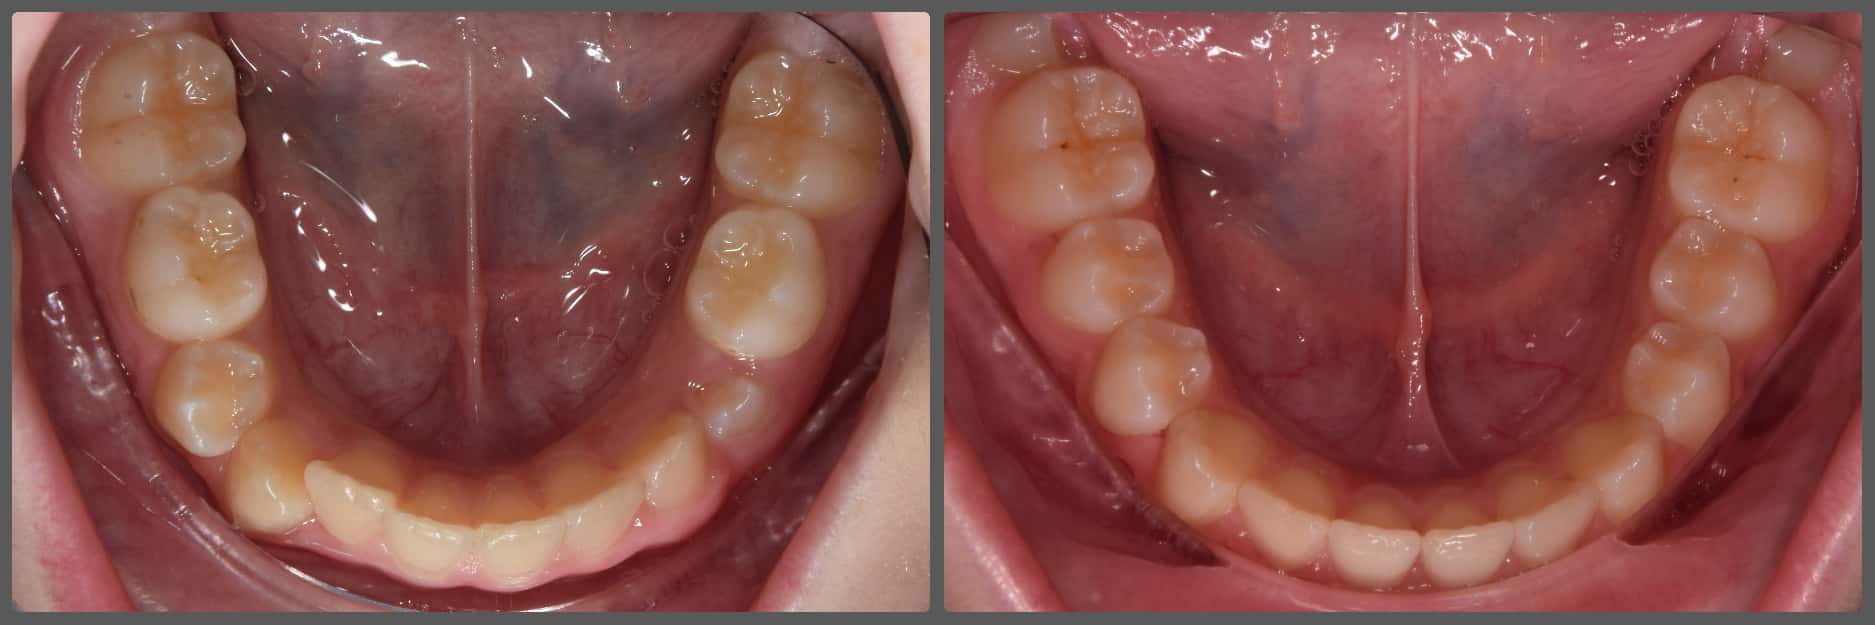

Zoli torlódott alsó fogai miatt szeretett volna fogszabályozó készüléket. Régebben 2 db felső kisőrlő fog eltávolításával már fogszabályozták, azonban az alsó fogív eltérései jelentősek voltak. A torlódás mellé közepes mértékű mélyharapás társult, valamint a bal oldali kisőrlő fogaknál non-occlusiot figyeltem meg. Ez azt jelenti, hogy esetünkben a felső első kisőrlő fog az alsó első és második kisőrlő fog közé, de azok külső felszínére harap. Ez a felső fogat kifelé, az alsókat befelé, a nyelv felé dönti és hosszútávon súlyos elváltozást okoz. Alsó-felső Pitts21 rögzített fogszabályzóval, intermaxilláris gumihúzással, harapásemelőkkel és tolórugókkal Zoli fogait nagyon gyorsan, 13 hónap alatt sikerült tökéletes pozícióba szabályoznunk, mind esztétikai, mind funkcionális szempontból (persze ehhez kellett a töretlen lelkesedése, együttműködése is). A kezelés végén az alsó fogívre fix retainert helyeztem fel az elért állapot megőrzésére. A végeredmény úgy gondolom mindent elmond!